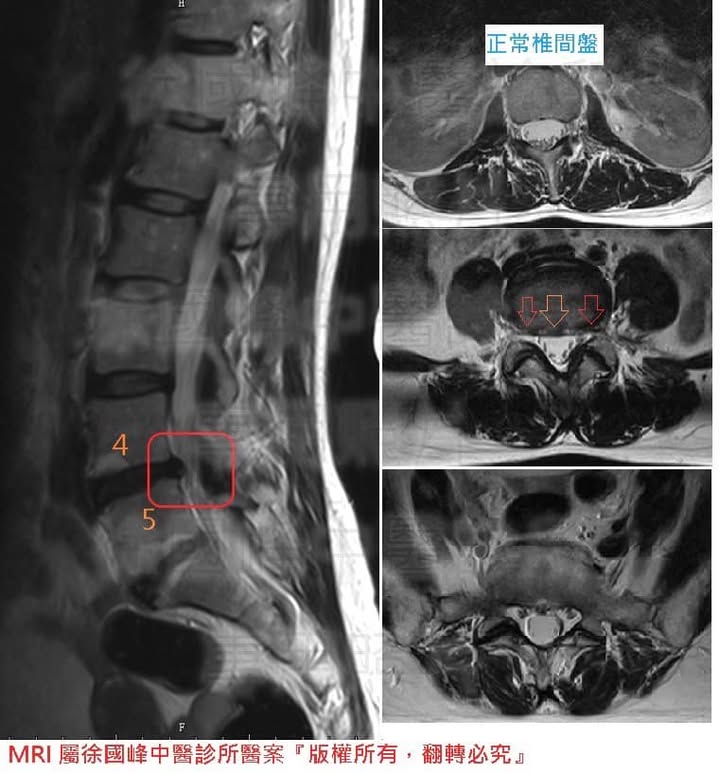

✅ 診斷:

1.L4L5椎間盤突出合併椎間韌帶拉傷

2.雙側臀小肌慢性筋膜發炎疼痛

3.梨狀肌症候群